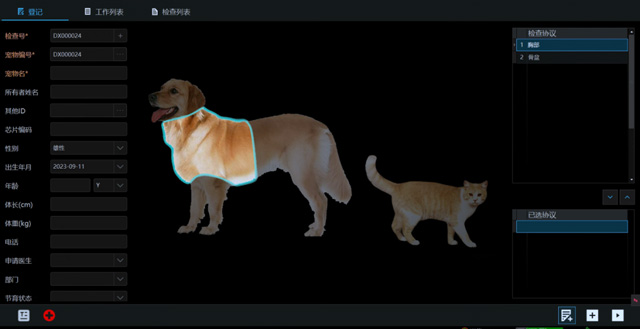

从临床角度出发,大力发展动态DR,以精准的诊断为小动物保驾护航。宠物DR升级使用双焦点球管,大尺寸平板探测器,超高频逆变高压发生器。医用纤维板台面,防止宠物划伤。宠物DR整机小巧实用,骨略结构和器官位置,分类详细,运算更快,让拍摄条件更科学,有助于提高诊断的准确性和效率。安装移动非常方便。低输入电流设计,220伏常规电压。多品种动物程序设定,满足各个临床需求。成像效果显著,宠物不能言语表达,导致误诊率居高不下。宠物诊疗均以经验诊断为主的方式,确保最小化辐射降低对医生及动物的影响。以满足精细化的宠物医疗需求,成为诊断宠物内外科疾病的必备工具。使医院更有竞争力,为医院创收增光添彩。